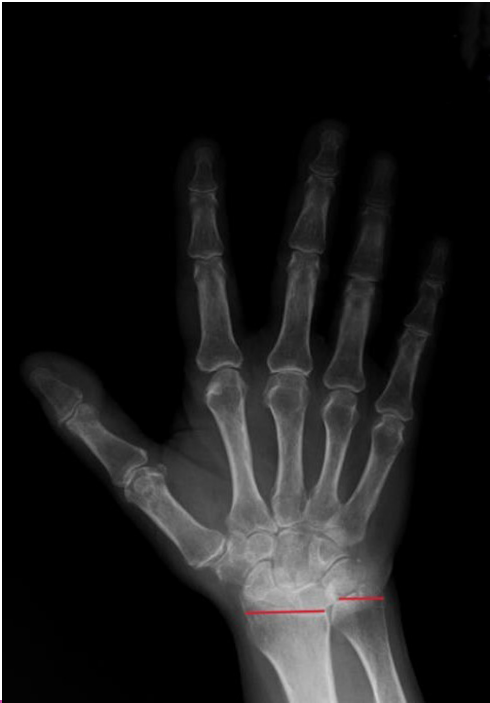

The radius and ulna are connected by the dorsal and volar radioulnar ligaments and are expected to be in a neutral position relative to each other within the wrist joint.[4] Ulnar variance is a term used to describe the positional relationship between the distal ulna and radius. Negative ulnar variance is the presence of the ulna 1 mm or more proximal to the radius and has been associated with conditions such as ulnar impingement syndrome, scapholunate dissociation, and Kienböck’s disease (Figure 1). Positive ulnar variance is the presence of the ulna 1 mm or more distal to the radius and is associated with conditions such as ulnar impaction syndrome, cartilaginous tears in the carpal bones, early degenerative changes, and triangular fibrocartilaginous complex (TFCC) tear (Figure 2).[5]

Hand and wrist radiographs were evaluated blindly by 2 rheumatologists (MP-SK). Hand radiographs were analyzed according to the Modified Sharp Score (MSS) system.7 The presence of any erosion or joint space narrowing (JSN) was used as a criterion to define “RA-type joint involvement (RJI).” “Severe joint involvement (SJI)” was defined as the presence of erosion with a score of 3 or higher or JSN with a score of 4 or more according to the MSS. Patients were also evaluated for ankylosis of any hand joint. Ulnar variance, as described by Hulten, was determined by measuring the distance between horizontal lines drawn at the subchondral bone of the distal radius, just beneath the articular cartilage, and the most distal subchondral border of the ulnar head.[8] A displacement of 1 mm or more of the ulna relative to the radius was defined as AUV. Radiographic evaluation was performed with full agreement; if there was disagreement between the readers, the X-ray was re-evaluated and an agreed final decision was made.

Ulnar variance defines the position of the ulna relative to the radius at the distal radioulnar joint, exhibiting increases during forearm pronation and decreases during supination.[9] Consequently, the standard approach commonly used to demonstrate ulnar variance is a method described in detail in Palmer’s study, which involves obtaining an X-ray with the shoulder abducted to 90 degrees, the elbow flexed to 90°, and the hand in a neutral position.[10] This method was used in the radiographs and evaluated the radiographs by measuring from the standard points defined by Hulten. Both methods have been shown to have high intraobserver and interobserver reliability in the literature.[9] In studies conducted on cadavers to assess ulnar variance, X-ray imaging was compared with dissection following the use of computed tomography (CT) and magnetic resonance imaging (MRI) techniques, leading to the conclusion that X-ray imaging may be sufficient for detecting ulnar variance.[10] Therefore, it was proposed that if routine X-ray imaging, commonly utilized in patients with RA, is performed using the Palmer method, both the disease findings and ulnar variance can be evaluated simultaneously without incurring additional costs.